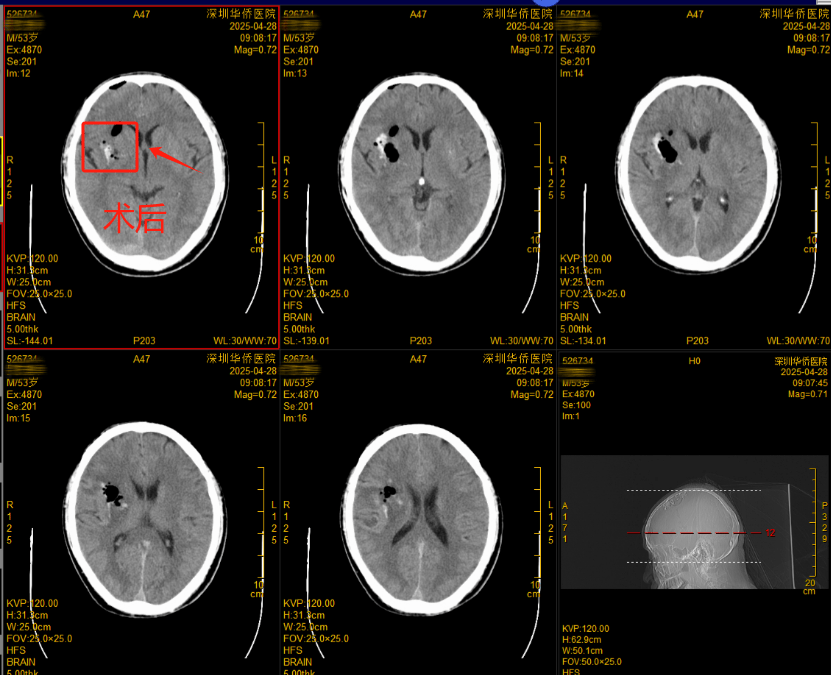

▲术后CT影像

神经内镜下颅内血肿清除术是一种先进的微创手术方式,具有诸多优势。与传统开颅手术相比,它具有创伤小、出血少、恢复快、并发症少等特点。通过微小的切口,借助内镜的高清视野,医生能够精准定位和清除血肿,最大程度地保护患者的神经功能,降低手术风险,缩短患者的住院时间。